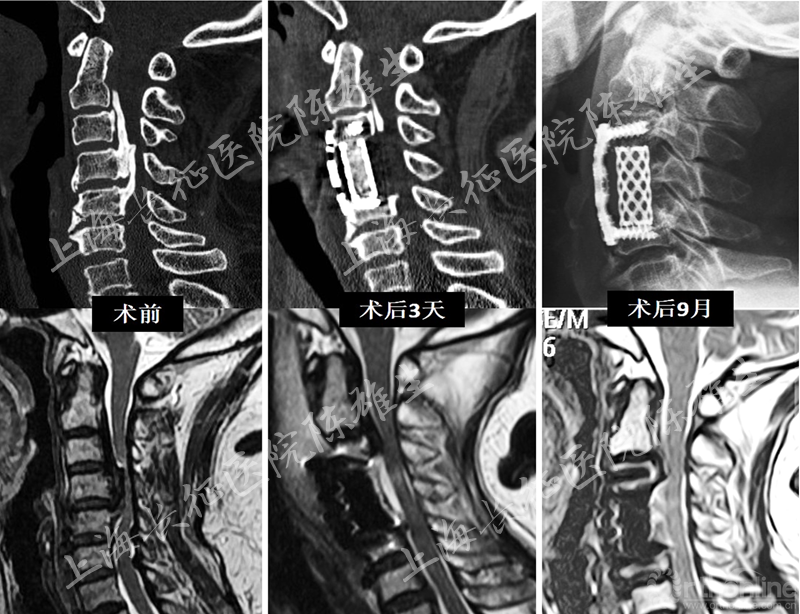

4. 典型病例介绍

张xx,女性,66岁。因“双上肢麻木无力1年半,行走不稳2月”入院。查体见双侧肱二头肌,肱三头肌肌力4级,双手握力3级,双下肢肌力4-级;四肢腱反射亢进,Hoffmann征(+),Babinski征(-)。影像学检查见C2-5 OPLL,椎管占有率=80%,C3-5脊髓受压变性。术中将1/2 C3+C4+ 1/2 C5椎体后壁和骨化物整块切除,切除过程发现有硬膜囊骨化,同时切除硬脊膜骨化物。术后脑脊液漏,加压包扎1周后改善;术后6月MRI见脊髓压迫解除,椎前间隙未见脑脊液征象,术后双手握力恢复至5-级。(图16)

图16